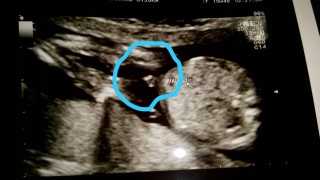

妊娠15w4d。 ♂の子です。 毎回顔を隠さず見せてくれます!